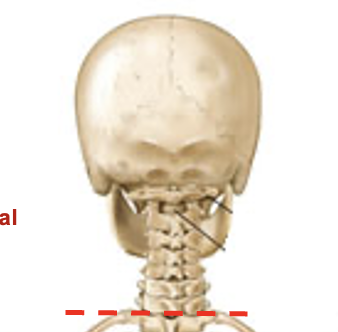

vertebrae

bones that make up the vertebral column, which is a casing that protects the spinal cord

32

number of vertebrae bones that make up the vertebral column

cervical

7 bones make up this segment of the vertebral column

thoracic

12 bones that make up this segment of the vertebral column

lumbar

5 bones that make up this part of the vertebral column

sacral

5 fused bones that make up this part of the vertebral column

coccyx (1)

3 fused bones that make up this part of the vertebral column (1)